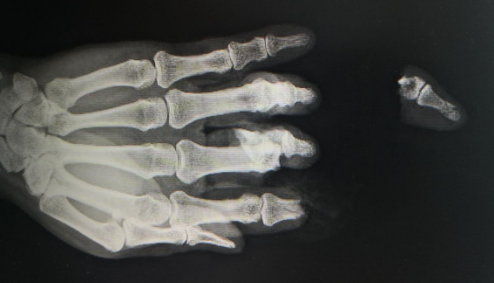

半个月前的一个下午,家住河南永城的胡师傅,在自家院子里加工红薯粉的时候,手指不小心绞入到了打粉机的三角带中,导致左手4根手指受伤,其中示中指完全离断,环小指关节、肌腱损伤。

而惊吓之后胡师傅慌忙处置,将断指直接放入冰块中冷冻,不曾想,这个举动差点造成了不可逆的严重后果。

据了解,胡师傅的女儿是当地医院的护士,胡师傅受伤后立即带着断指来到女儿工作的医院,当地医院医生接诊后看到胡师傅的断指已经被冰块融化的冰水完全浸泡,于是立刻指导他行纱布包裹后放入塑料袋中再在其周围放入冰块冷藏保存后,紧急转到我院。

胡师傅入院后,医生查看其示指指体中段、指端部分毁损,因为断指被冰水直接浸泡,导致离体指冻伤,中指近节部分指体、中节指体毁损,几乎无再植条件,但是胡师傅断指再植的意愿非常强烈,于是betway在线登陆手外科潘勇医生决定给予示指中节短缩再植,指尖残端修整,中指中节指骨短缩再植。由于手指有缺失,血管管径不匹配,近端约0.8mm,远端约0.3mm,均属于超级显微外科范畴,对血管吻合技术要求非常高。经过五个多小时的“精雕细琢般的修复”手术,将那些细微的血管、神经,使用比发丝细得多的缝线一一缝合,血管顺利通血,手指逐渐恢复了血色,手术圆满完成!